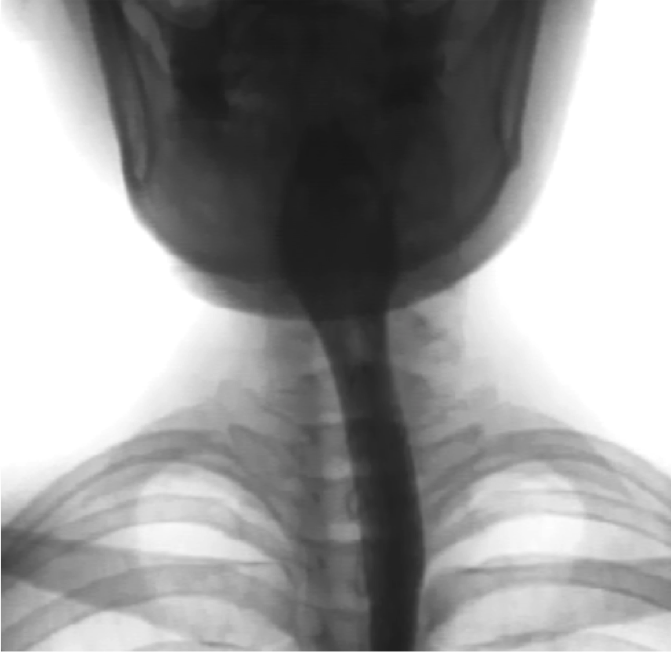

2. 嚥下造影検査(VF)

レントゲン室で車椅子に座った状態でバリウムの入った数種類の検査食品を食べたり飲んだりしていただく検査です。口に入った検査食品がどのように送り込まれていくかをレントゲンで確認します。